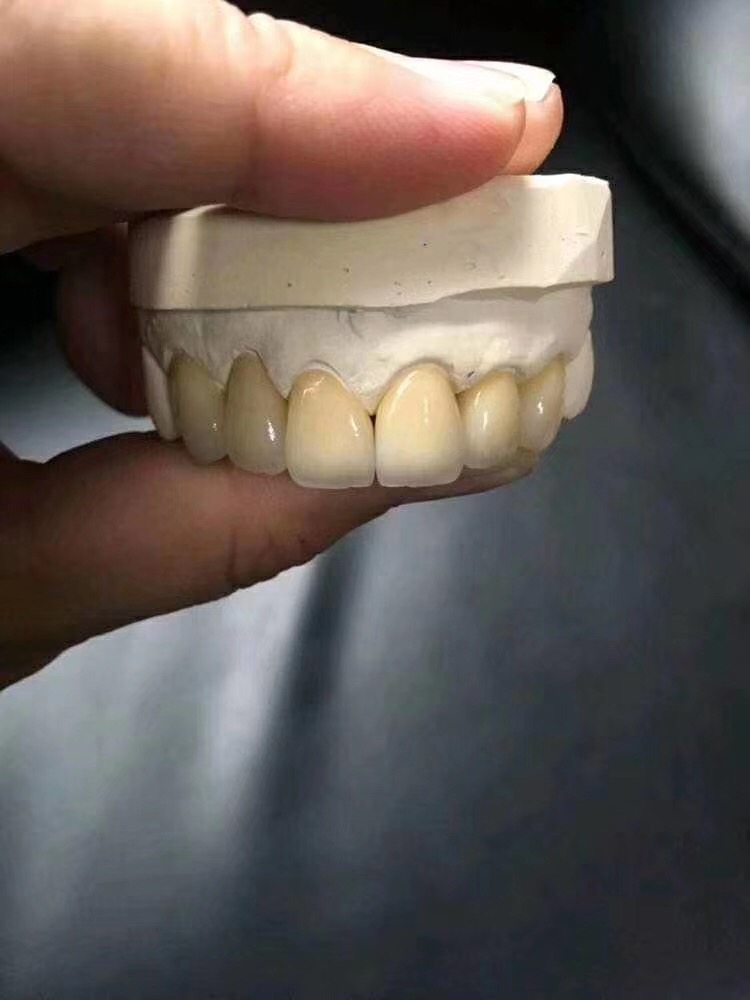

另外需要强调的是,做完根管治疗的牙齿质地比较脆,如果牙齿平时受力较多,或者治疗前因创伤/龋齿造成牙体缺损过多,医生会建议您做一个牙冠将它保护起来。这个就之后再讲了。

根管治疗后需要做牙冠吗?

很多朋友说了:牙齿都不疼了,补好了,为何还要做牙冠呢?

因此根管治疗后一定要做个牙冠将其保护起来。

牙套就是指的烤瓷牙或者全瓷牙: